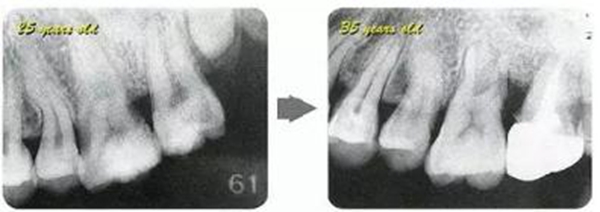

右邊參考病例

①的患者是35歲女性。4~10mm的牙周袋和大量的牙石。特別是在左上、右下、左下的磨牙處能看到大量牙槽骨吸收。這名患者是慢性牙周炎,僅在磨牙處有局部由風險因子導致(解剖學形態(tài))導致的重度病癥發(fā)展。

另一方面25歲女性的參考病例

②將會是什么樣的呢?左上、右下、左下的磨牙處有大量牙槽骨吸收,考慮到其發(fā)病年齡,斷定為是侵襲性牙周炎局部型。

但是實際上參考病例①和②是同名患者,①是②10年后的狀態(tài)。這名患者間隔10年后來就診,讓我們可以確認到癥狀的變化。

●參考病例② 25歲女性

25歲女性。菌斑控制狀態(tài)不好。齦溝除磨牙處外全在3mm以下,X光照片上左上、右下、左下的第一磨牙上有垂直性骨吸收。這個病例是參考病例①10年前的狀態(tài),是典型的侵襲性牙周炎局部型。

牙周病的發(fā)展因部位不同而發(fā)展程度不同的。10點后的狀態(tài)參考病例①和參考病例②的磨牙處的狀態(tài)相比較,思考下沒接受治療病情發(fā)展的特別性吧。

參考病例① 35歲女性

在左下第一磨牙在25歲時近中處可以看到垂直性的骨吸收,但35歲時吸收停止,原本沒有見到的遠中處骨吸收的,現(xiàn)在卻吸收得很嚴重。

在右下處,原本有大量骨吸收的第一磨牙處的吸收卻變緩慢,原本沒有吸收的第二前磨牙卻出現(xiàn)了吸收。出現(xiàn)吸收的左上第一磨牙的遠中處,吸收得越來越多了。

把10年間的變化做成表格。牙周病的發(fā)展根據(jù)各個人會不同,即使通一個人,不同牙齒,不同牙面發(fā)展的狀態(tài)也不同。